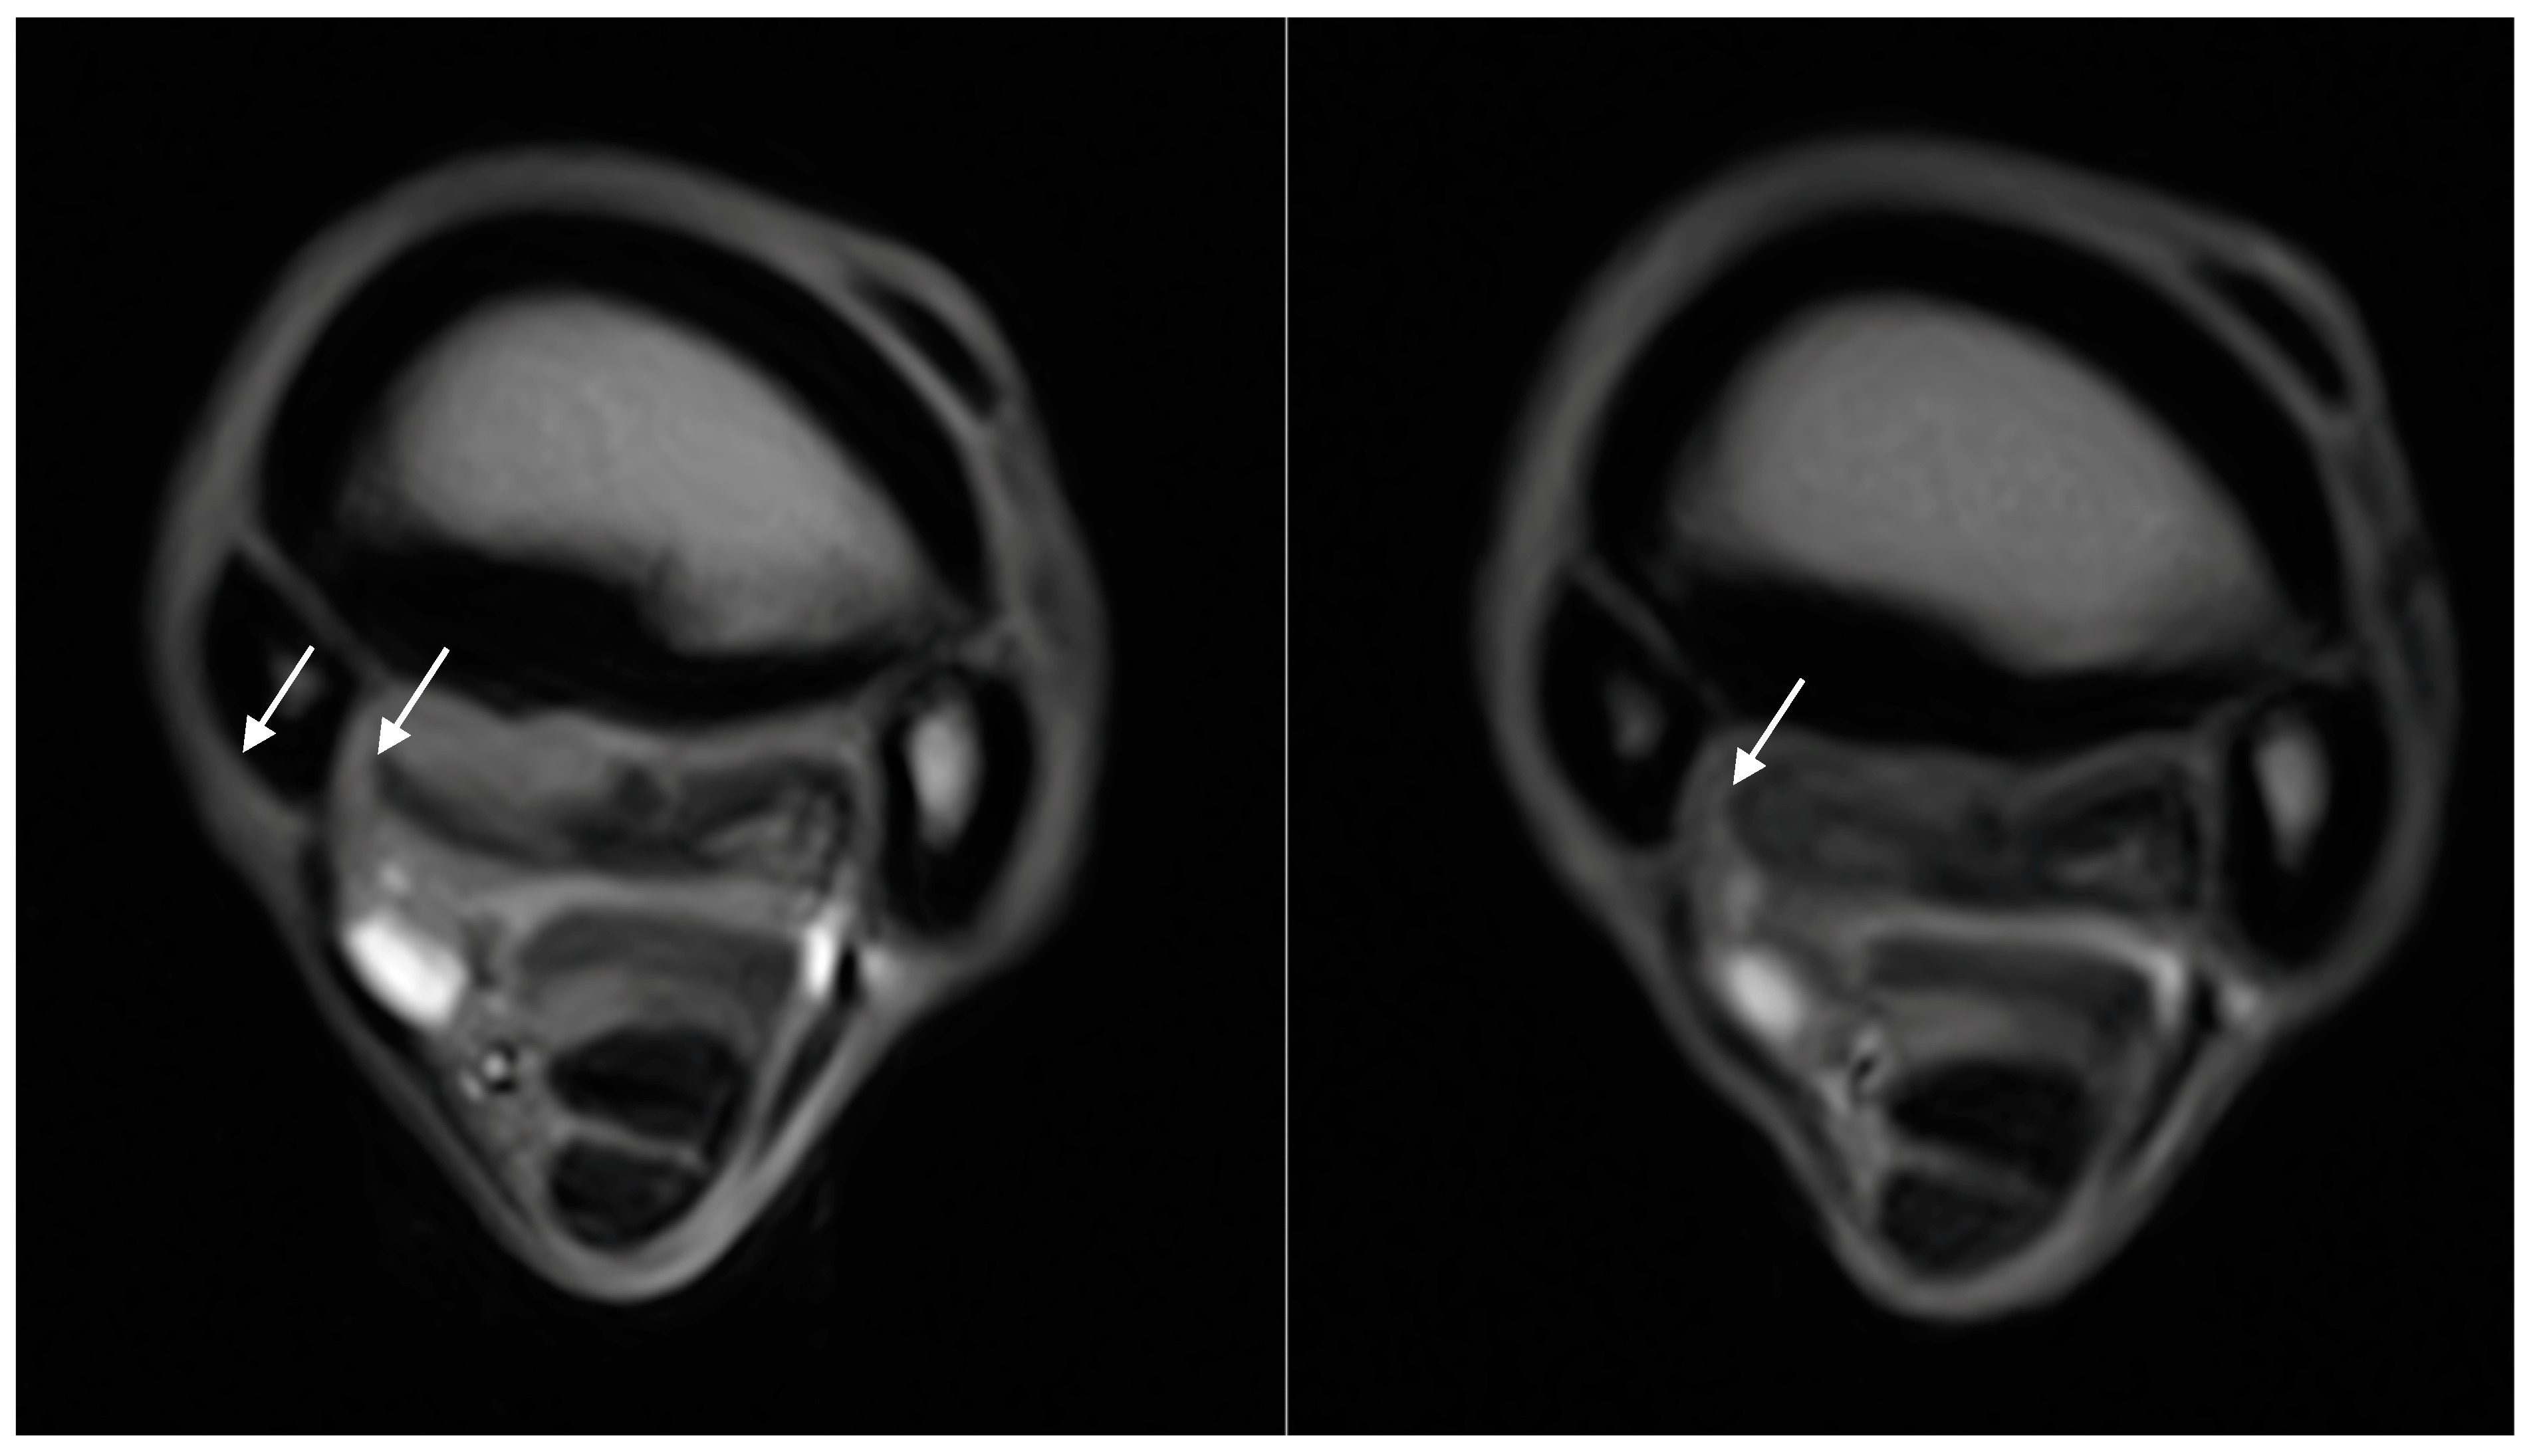

| Dorsal margin irregularity of the PSL | 12/18 (75%) | - | - | 12/12 (100%) | - |

| Dorsal margin irregularity of the PSL | Grade 0: 5 limbs Grade 1: 7 limbs Grade 2: 6 limbs Grade 3: 0 limbs | Grade 0: 5 limbs Grade 1: 7 limbs Grade 2: 6 limbs Grade 3: 0 limbs |

| McIII sclerosis | 18/18 (100%) | - | - | 16/18 (89%) | 2/18 (11%) |

| McIII sclerosis | Grade 0: 0 limbs Grade 1: 11 limbs Grade 2: 6 limbs Grade 3: 1 limb | Grade 0: 0 limbs Grade 1: 10 limbs Grade 2: 6 limbs Grade 3: 2 limbs |